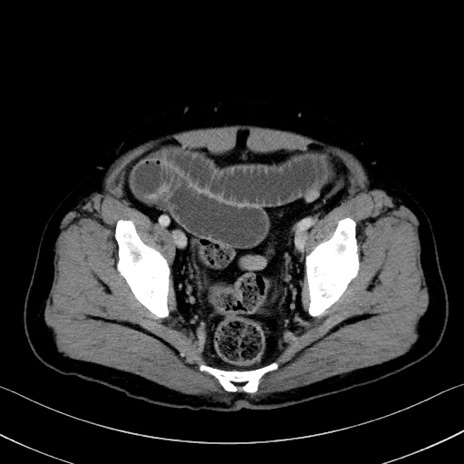

症例35(横断像)

【症例】70歳代 男性

【主訴】腹部膨満、嘔吐

【現病歴】昨日より腹部膨満感出現。本日増悪し、仙痛出現。嘔吐あり、受診。

【既往歴】糖尿病、胆摘後

【身体所見】BP 149/80mmHg、HR 74/min、BT 35.9℃、腹部:膨満、軟、圧痛なし。腸雑音減弱あり。上腹部正中切開瘢痕あり。

【データ】WBC 13500、CRP 1.72